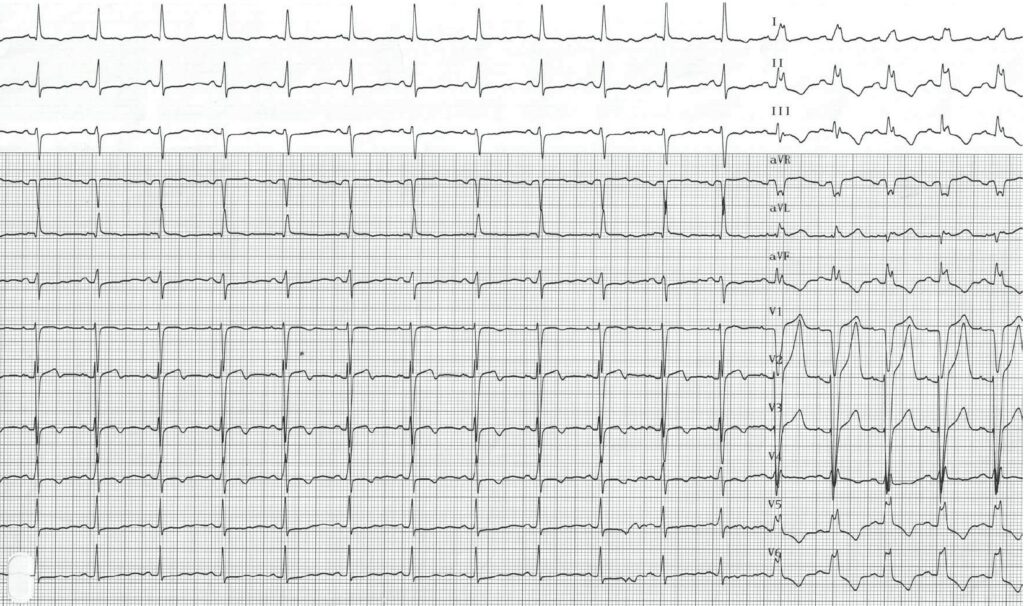

Tracé inverse; à la faveur d’un léger ralentissement, disparition de l’aspect de bloc de branche gauche et retour des QRS fins;

Cette jeune patiente présentait des douleurs thoraciques typiques en l’absence d’antécédent notable ou de facteurs de risque. Ces douleurs apparaissaient pour des efforts relativement modestes. L’électrocardiogramme réalisé au repos montrait des complexes QRS fins de morphologie et de durée normales, une repolarisation sans anomalie. Un électrocardiogramme d’effort a été enregistré avec mise en évidence pour une augmentation limitée de la fréquence cardiaque, d’un aspect de bloc de branche gauche typique contemporain de la survenue de la douleur. A l’arrêt de l’effort, la normalisation du tracé s’accompagnait de la disparition de la douleur. L’échographie cardiaque était normale. Une coronarographie mettait en évidence des artères coronaires saines sans possibilité de déclencher un spasme.